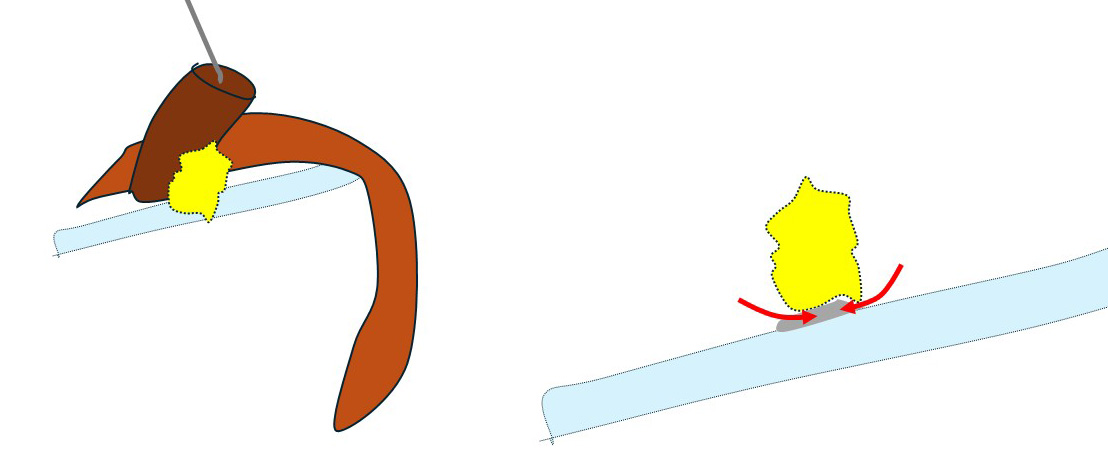

このように(左図)鎖骨下静脈と鎖骨下リンパ節の関係を(何にも邪魔されずに)直視できる+(鎖骨下リンパ節が持ち上がることによって)「鎖骨下静脈と鎖骨下リンパ節の「接合面」を直視できるのです。(右図)

(矢印のように)慎重に左右から少しずつ外していき、遂に「郭清完了!」となったのです。